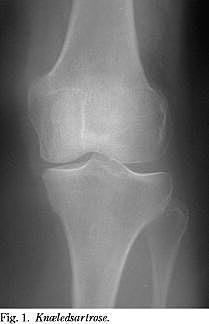

1. Hvilke udsagn om kirurgisk behandling ved symptomgivende etkammerartrose (Fig. 1) er korrekte?